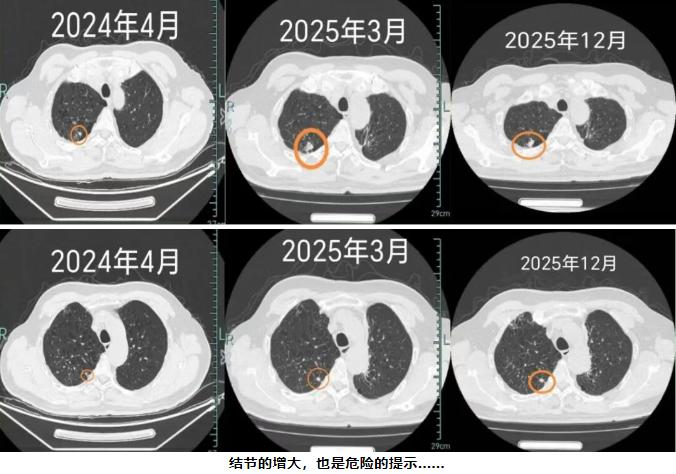

可同期检查中,医生还发现张先生的右上肺有两个较小的结节,建议他先通过定期随访来观察情况,在接下来的一年半的复查中,医生告诉张先生:“你看这两个结节,一年多已经长大了不少了,我们建议立即手术治疗。”张先生忙不迭点头:“都听医生的,我一定好好治病!”

手术台上,术中冰冻病理检查提示张先生为低分化癌,属于恶性程度较高的肿瘤类型,治疗团队马上为患者实施了右上肺叶切除+纵隔淋巴结清扫术。令人欣慰的是,病理结果显示两个结节都是浸润性癌,但由于发现及时、手术果断,患者的淋巴结并未出现转移。